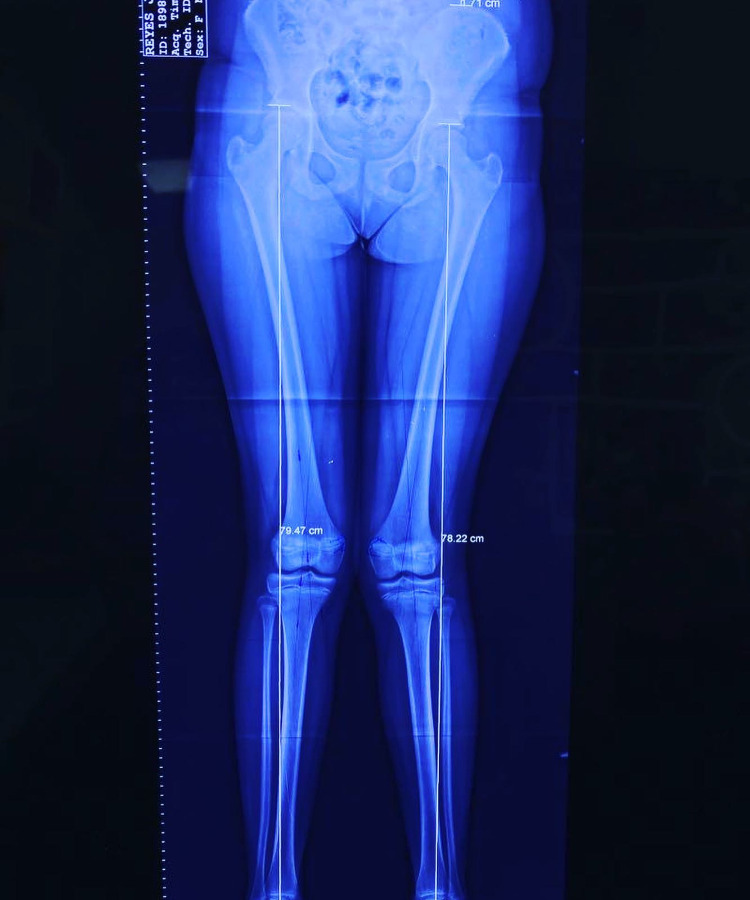

Rodillas en Valgo

conocer másLas deformidades de pie y rodilla incluyen genu varo, genu valgo, pie plano y pie cavo, con causas congénitas o postraumáticas.